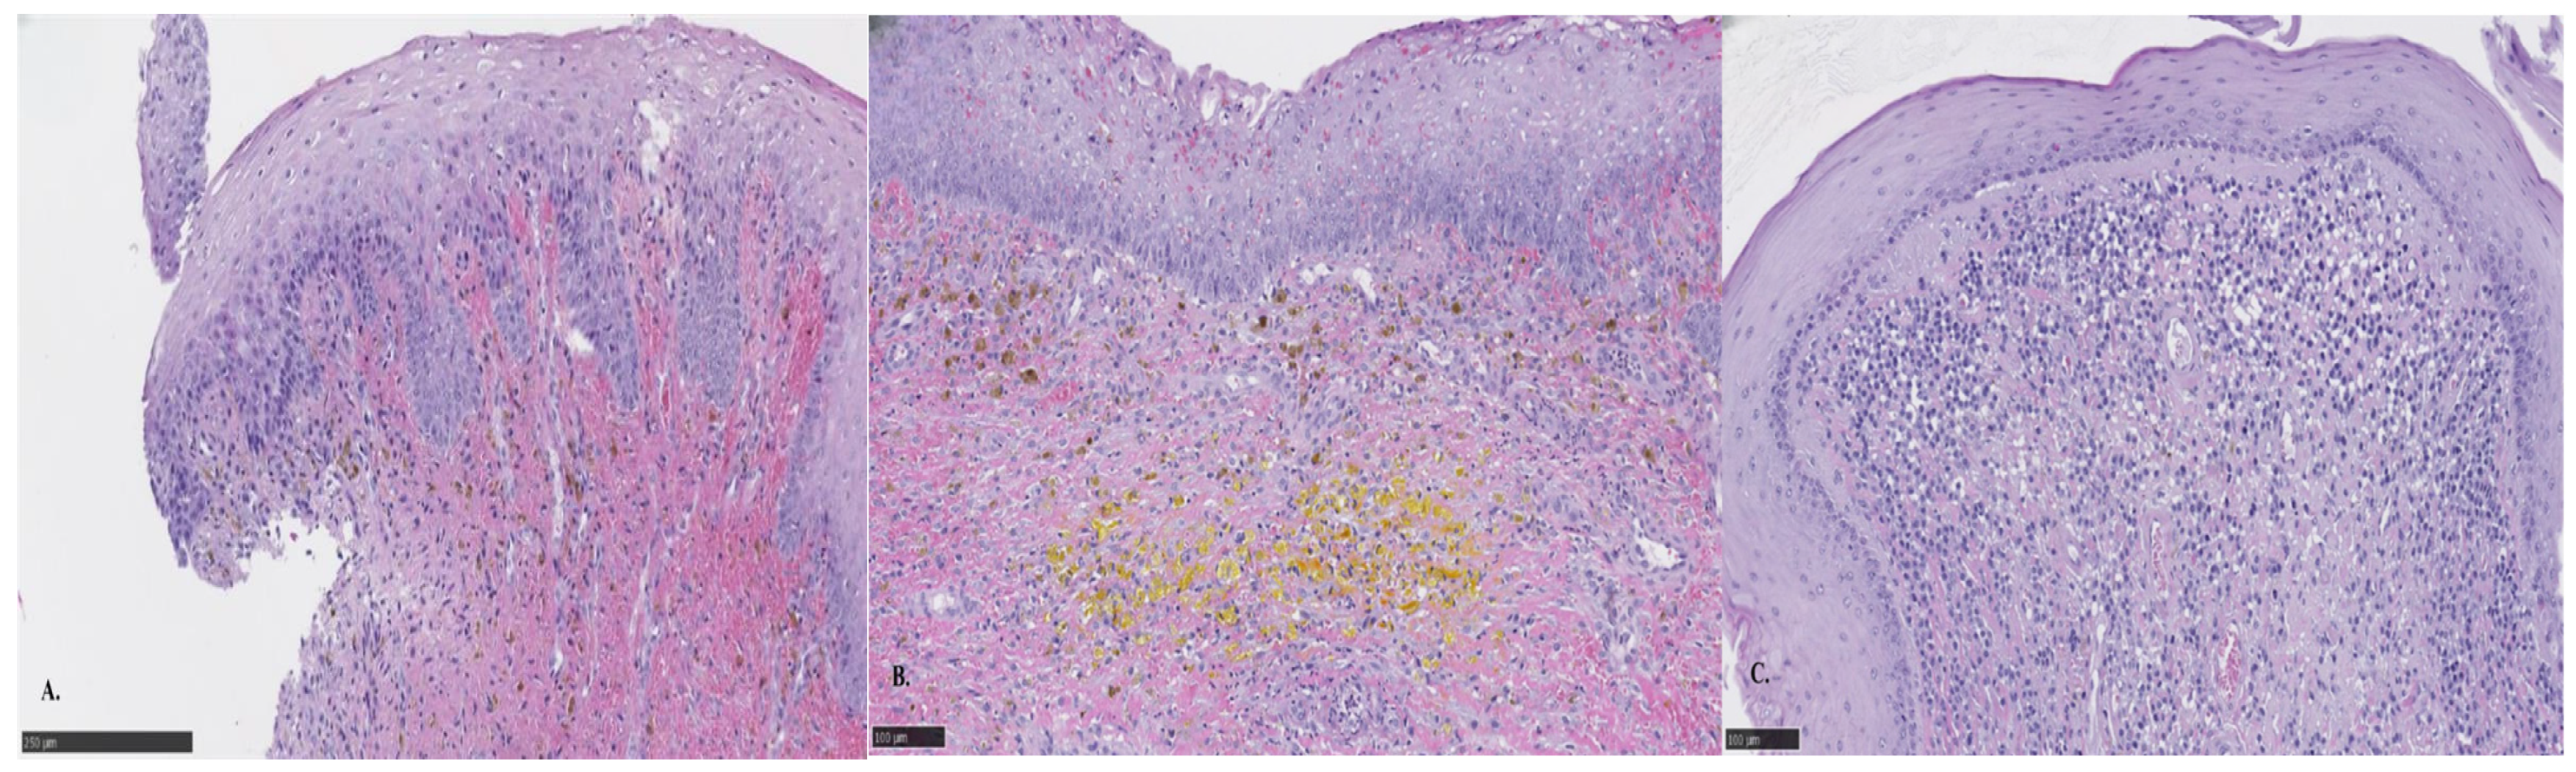

Histopathologic results indicated both proliferative and inflammatory changes suggestive of an inflammatory polyp. These included moderate diffuse chronic lymphocytic, histiocytic, and neutrophilic inflammation, with epithelial hyperplasia, fibroplasia, hemorrhage, and hemosiderin. A dense population of round cells was also noted but interpreted to be part of an inflammatory reaction (Figure 3). A contrast computed tomography (CT) was performed (Figure 4) and surgery was recommended for mass removal.

Figure 3.

Histopathology of endoscopically obtained biopsy samples of the mass (hematoxylin and eosin stain). (A) The surface epithelium is thickened, indicating hyperplasia, and is supported by abundant fibrous connective tissue. (B) The lamina propria contains moderate number of macrophages laden with hemosiderin and hematoidin. (C) There is a dense population of large round cells interspersed by lymphocytes and neutrophils.